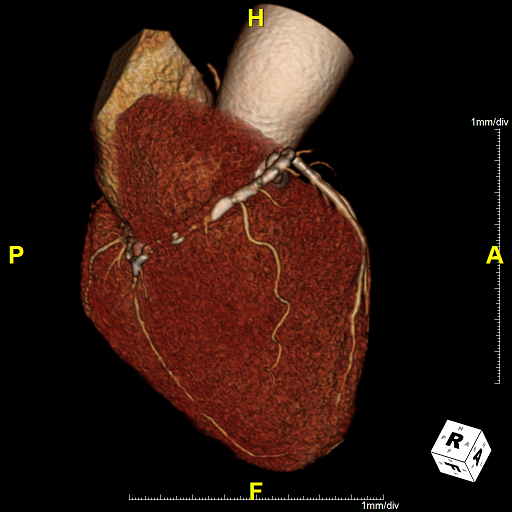

CTでは、心臓に酸素や栄養を送る冠動脈と呼ばれる血管の状態(狭窄や閉塞)や、心臓の全体像を知ることができます。また、バイパスなど手術後の経過なども調べることができます。

PCI後の冠動脈評価CT